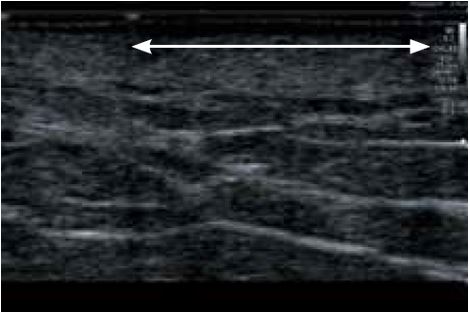

Перелом ребер

57-річна пацієнтка звернулася зі скаргами на біль у правому верхньому підребер'ї. Проте, незважаючи на численні обстеження, причину болю не було встановлено. При використанні датчика 7 МГц (PLT-704SBT, Aplio 500) (мал. 2а) структура ребер виглядала нормальною. Однак датчик надвисокої частоти виявив невеликий перелом ребра (рис. 2б), який потім був ідентифікований як причина болю. Ці невеликі переломи не могли бути діагностовані іншими методами візуалізації, що підкреслює чіткість і деталізацію, які забезпечує PLI-2004BX.

a) PLT-704SBT (Aplio 500)

б) PLI-2004BX (Aplio i-серії)

Малюнок 2. Зображення перелому ребер, отримані за допомогою PLT-704SBT (7 МГц) (а) та PLI-2004BX (24 МГц) (б).